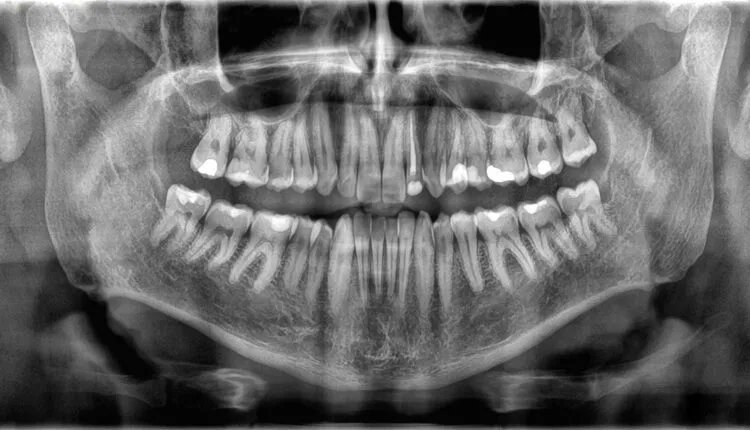

Γιατί τα δόντια δεν θεωρούνται οστά;

Αρχικά, τα δόντια και τα οστά φαίνονται παρόμοια. Αλλά γιατί τα δόντια δεν θεωρούνται τύπος οστού;

Αφού τα δόντια μοιάζουν πολύ με τα οστά: και τα δύο είναι σκληρά, λευκά και πλούσια σε ασβέστιο. Παρά τις λίγες βασικές ομοιότητες, στην πραγματικότητα είναι αρκετά διαφορετικά.